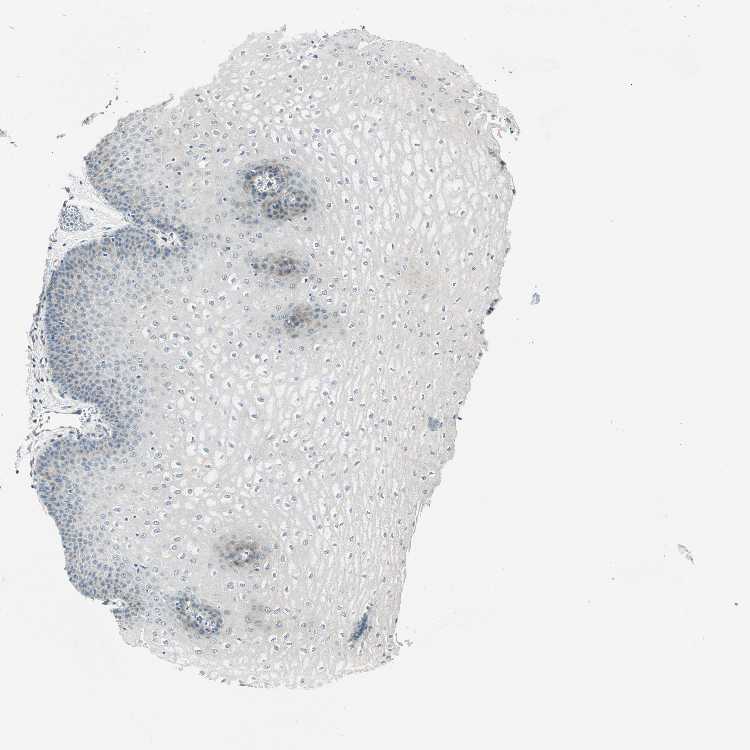

ESOPHAGUS - Antibody stainingi

Antibody staining in the annotated cell types in the current human tissue is reported as not detected, low, medium, or high, based on conventional immunohistochemistry profiling in selected tissues. This score is based on the combination of the staining intensity and fraction of stained cells.

Each image is clickable and will lead to virtual microscopy that enables deeper exploration of all samples and also displays staining intensity scores, fraction scores and subcellular localization as well as patient and tissue information for each sample.

Antibody HPA006379

Squamous epithelial cells Not detected